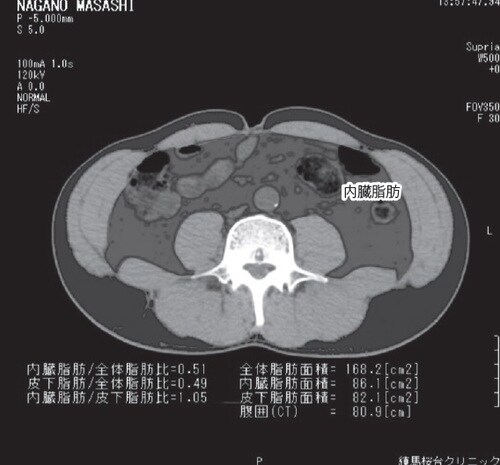

そこで、どれくらい内臓脂肪が蓄積しているのかを測定できるのが「ファットスキャン」という検査です。これは、おへそのレベルで撮影したCT画像から脂肪組織の面積を測定する方法で、内臓脂肪の面積が100㎠以上になると内臓脂肪過多と判定されます。

筆者の場合は、減量をしてマラソンを続けているとはいえ、もともと体質的にも糖尿病になりやすいこともあり、内臓脂肪まで溜まっていたのではリスクを高めてしまいます。そこで、ファットスキャン検査を受けてみたところ、内臓脂肪は正常の範囲だったのです。

しかし、まだ減らせる量の脂肪がついていたため、さらに体を引き締めなければいけないことを視覚的にも確認できました。画像を見ると、頑張って減量しているだけにショックでした。ファットスキャン検査は、早い時期に筆者のクリニックでも導入しています。内臓脂肪を推定するのに効果的で、しかも一目瞭然で分かりやすい検査にもかかわらず、希望者はあまりいないのが残念でなりません。